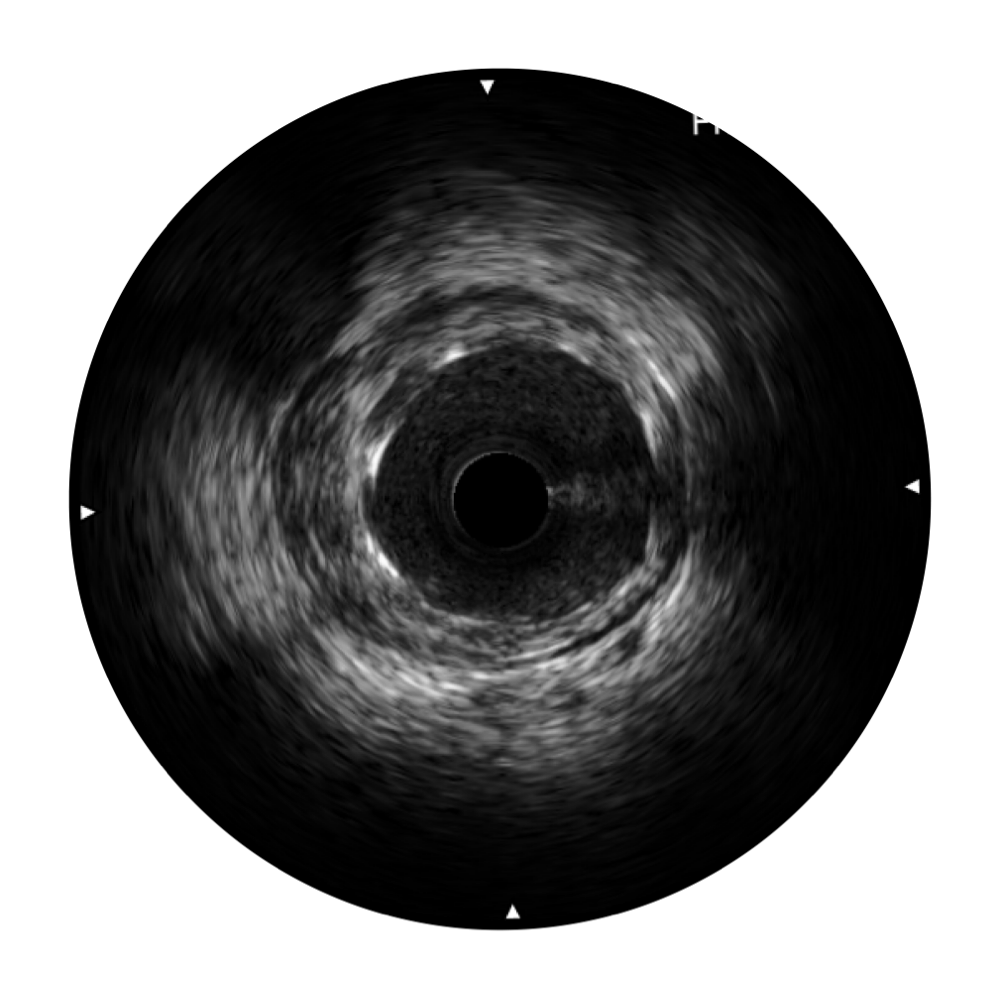

DB中国旗舰官方网站宽频IVUS图像

传统IVUS图像

对比传统IVUS导管成像,DB中国旗舰官方网站宽频IVUS图像的近场支架梁显影更细腻,远场中膜外血管仍清晰可辨,兼顾远中近,兼顾分辨力与穿透深度